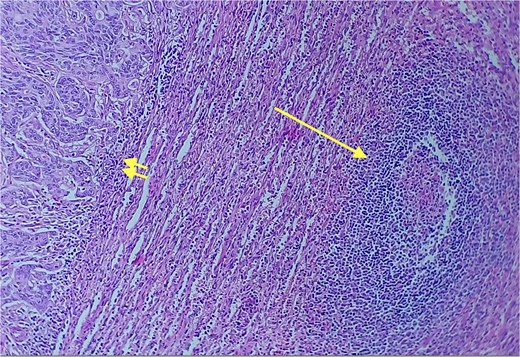

Given the histopathological findings, a laparoscopic splenectomy was performed in a second operative session. The procedure was carried out in the left lateral decubitus position using three trocars. Intraoperatively, a 3 × 3 cm lesion was identified within the splenic parenchyma. The specimen (Fig. 6) was extracted through the previously used Pfannenstiel incision. Histopathological analysis confirmed infiltration by an enteric-type adenocarcinoma (Figs 7–9).

Red and white pulp of the splenic parenchyma (arrow) with infiltration by intestinal-type adenocarcinoma (double arrow, left); H&E ×200.